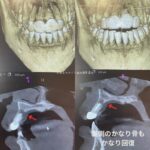

20代女性 上の歯の突出感・隙間・下の歯の叢生(そうせい:がたつきのある歯並びという意味)の改善を求めて御来院してくださいました。下の顎が小さく、下の歯が重なって生えています。

矯正前の写真2枚

インビザラインで抜歯矯正を計画しました。枚数は50枚 期間はおよそ1年半のプランです。